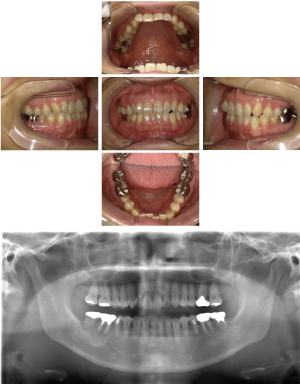

40代 女性 インプラント治療(GBR)

| 年代・性別 | 40代・女性 |

|---|---|

| 主訴 | 硬いものが咬めなくなってきたため、咬めるようになりたい。 |

| 部位 | 右上⑥5④ 右下6 上顎②11② |

| 治療期間 | 約1年2ヶ月 |

| 費用 | ¥2,099,900(税込) |

| 副作用・リスク |

|